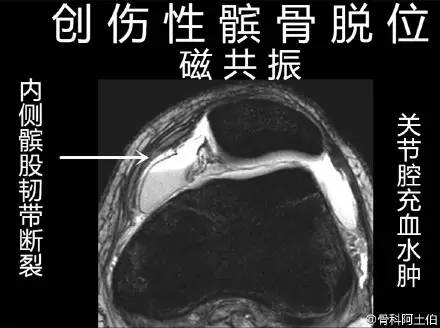

髌骨脱位绝大部分是向外侧脱位,脱位后,髌股关节内侧的稳定结构,包括髌股关节内侧支持带、股内侧肌、内侧髌股韧带都会受到损伤。